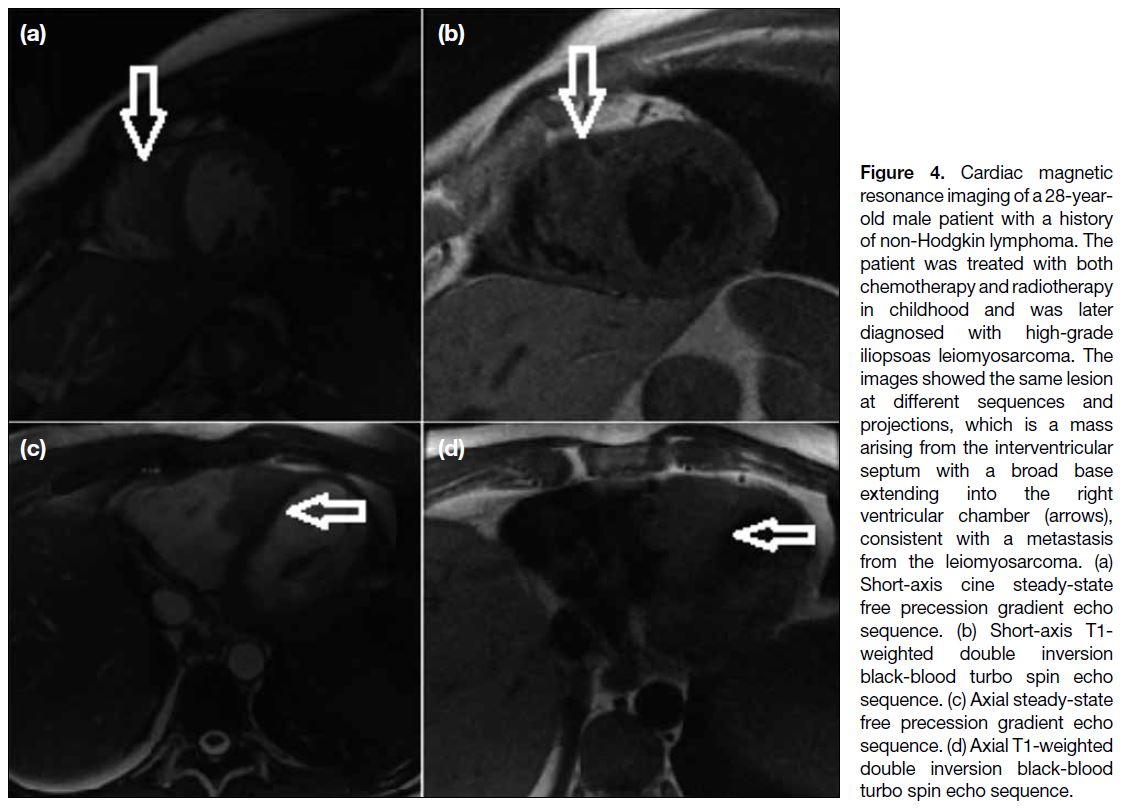

Figures 3 and 4 demonstrate the myocardial metastasis

of a uterine leiomyosarcoma and an iliopsoas muscle

sarcoma, respectively. Figures 5 and 6 depict the

Figure 4. Cardiac magnetic

resonance imaging of a 28-year-old

male patient with a history

of non-Hodgkin lymphoma. The

patient was treated with both

chemotherapy and radiotherapy

in childhood and was later

diagnosed with high-grade

iliopsoas leiomyosarcoma. The

images showed the same lesion

at different sequences and

projections, which is a mass

arising from the interventricular

septum with a broad base

extending into the right

ventricular chamber (arrows),

consistent with a metastasis

from the leiomyosarcoma. (a)

Short-axis cine steady-state

free precession gradient echo

sequence. (b) Short-axis T1-weighted double inversion

black-blood turbo spin echo

sequence. (c) Axial steady-state

sequence. (d) Axial T1-weighted

double inversion black-blood

turbo spin echo sequence.